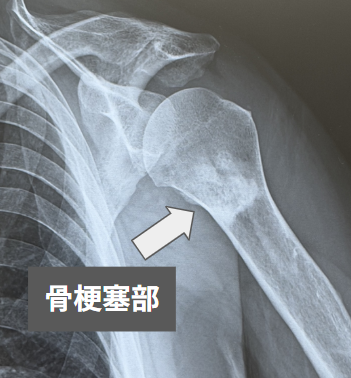

骨梗塞

骨梗塞(こつこうそく:bone infarction)とは、骨の内部に血液を送る動脈の流れが途絶えることで、骨組織が壊死してしまう病態です。一般に、股関節に生じる大腿骨頭壊死などの関節近傍の病変とは区別され、主に大腿骨遠位部や脛骨近位部など、長管骨の骨幹端から骨幹部にかけてみられます。「骨壊死」という言葉は比較的小さな病変を含めて広く使われますが、「骨梗塞」は通常、このような骨幹端部から骨幹部に及ぶ広範囲の骨壊死を指します。病変は単発のこともあれば多発することもあり、画像上は内軟骨腫などの良性骨腫瘍とよく似た外観を示すことがあります。

骨梗塞は、初期には単純X線検査(レントゲン)で異常を見つけにくく、他の症状の精査でMRIを行った際に偶然発見されることもあります。病変が進むと、単純X線検査では、骨内に「smoke-ring(煙の輪)」と表現される境界明瞭な不規則石灰化像や硬化像がみられます。